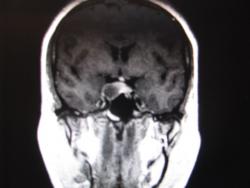

Макроаденома гипофиза.

Я бы добавила -кистозная.

Но на Т1 я не увидел "чистого" гипоинтенсивного сигнала соответствующего жидкости?

за счет жидкостного содержимого может говормить феномен седиментации, может содержимое с коллоидным компонентом.

Так могла бы выглядеть киста кармана Ратке?